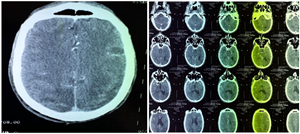

Escherichia Coli Brain Abscess in an Immunocompetent Adult: Case Report

El Fargani R., Idalene M., Ait Driss W., Tassi N.

International Journal of Innovative Research in Medical Science·April 19, 2025